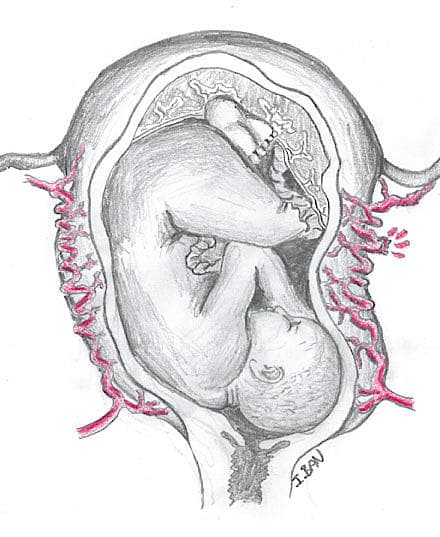

Taksigelse: Vi takker Ilija Ban, Hvidovre Hospital, for tegning.